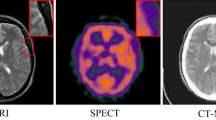

Image fusion has recently become a hot topic because of its applications in medical diagnosis. In several medical specialties, such as neurology, cancer, cardiology, and orthopedics, medical image fusion techniques help to enhance the diagnostic data available to medical practitioners, raising the standard of medical diagnosis and promoting more effective treatment planning. The single-modality medical picture cannot capture all the features of tissues or organs. For instance, computed tomography (CT) images provide detailed structural information on bones and implants, while magnetic resonance images (MRI) provide structural information on organs, soft tissues, and tumors but cannot detect calcification or lesions within bone tissues or human metabolic activity. In medical imaging, MR images are classified into T1-weighted (MR-T1) and T2-weighted (MR-T2) based on the variation of the radio frequency over time. MR-T1 visualizes anatomy and provides good contrast between different structures, while MR-T2 images evaluate pathology and abnormalities in soft tissues, both related to fatty acids and water content. MR-proton density (MR-PD) weighted images manifest when there is a reduction in the contrast of both T1 and T2 MR images. A radiologist might need to combine unique details from several modalities without compromising the localization characteristics of the source image. The integration of CT and MRI is beneficial for brain tumor surgery, as it provides a unified image that simultaneously captures both bone and tumor structures. Additionally, combining several MRI modalities shows superior tissue lesions and aids in analyzing tumor progression for a more thorough clinical diagnosis13.

The architecture of the proposed fusion method is shown in Fig. 4 by using one sample pair of CT (\(I_1\)) and MRI (\(I_2\)) images. At first, we decomposed both the images into two different subimages: base subimages (\(B_1\) and \(B_2\)) and detailed subimages (\(D_1\) and \(D_2\)). The base layer involves more crucial information, and the detail layer reflects texture information. Next, we employ the proposed similarity measure on base subimages to extract the features. Thus, we have obtained enhanced base subimages \(IFSMI_1\) and \(IFSMI_2\). Then, we decomposed these images into blocks of size \(2\times 2\) and reconstructed fused images using Eq. (14). Thus, we obtained base fused image \(B_{fused}\). After that, we fuse detailed images (\(D_1\) & \(D_2\)) using Eq. (15). The detailed sub-images present the approximate features of the medical images, and the coefficient amplitude provides sufficient information for fusion. The final fused image (\(I_{fused}\)) is computed by using Eq. (16). We have compared our proposed method with some recent image fusion methods, including IFS-based method3 and four other SOTA methods PCA-DWT24, CNP-MIF53, DTNP-MIF54, MDLSR-RFM16. Jiang et al.3’s method is constructed using IFSM, PCA-DWT is a hybrid method of PCA and DWT, CNP-MIF and DTNP-MIF are NSCT domain-based methods, and MDLSR-RFM is an SR-based model. The program codes for these methods are readily available to the public or provided directly by the authors. To ensure a fair and unbiased comparison, all parameters are set according to the recommendations specified in the relevant scholarly articles. Three distinct datasets, labeled 1, 2, and 3, are considered for comparison. Dataset 1 contains five pairs of CT and MRI images, as depicted in Fig. 6. Dataset 2 consists of five pairs of MR-T2 and MR-PD images, as shown in Fig. 7. Dataset 3 includes three pairs of MR-T1 and MR-T2 images, as shown in Fig. 8. The subjective and objective assessment of the results obtained is provided in the following sections.